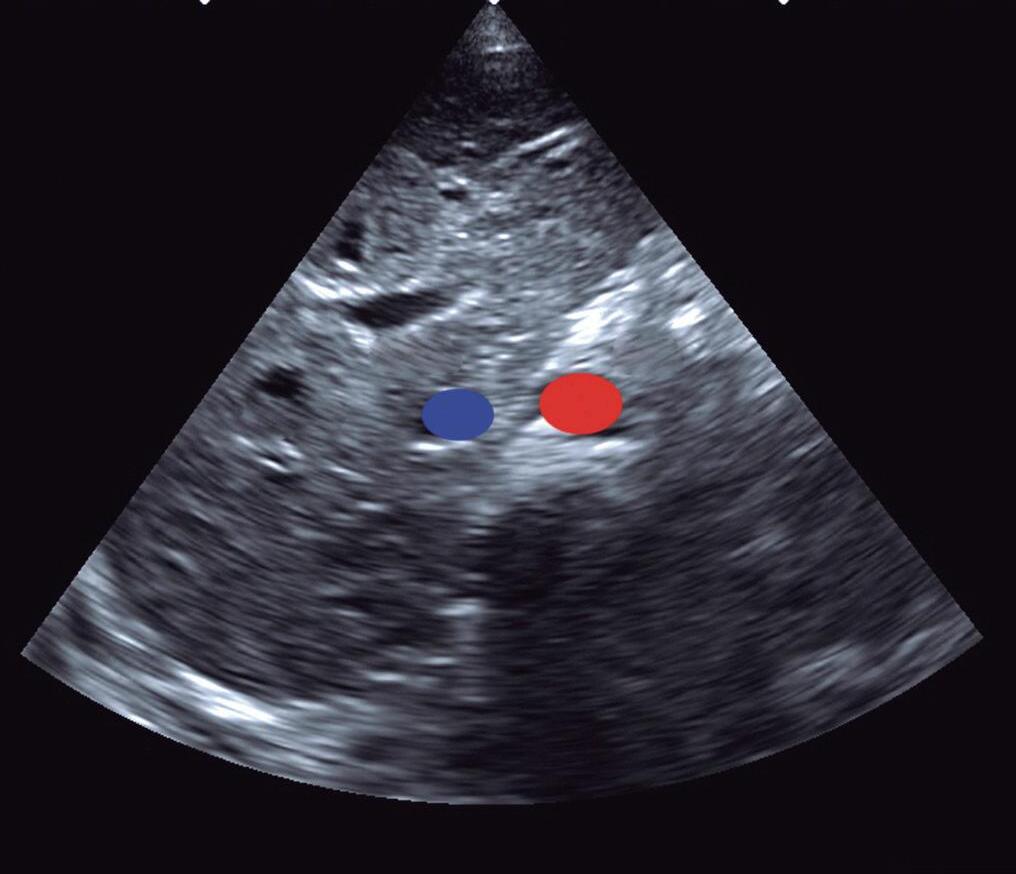

A veia cava inferior (VCI) e a aorta abdominal em eixo curto podem ser visualizadas nesse plano, com o transdutor abaixo do apêndice xifoide do paciente, perpendicular ao abdômen superior e com o index apontado para a esquerda do paciente, na posição de “3 horas” (▶ Vídeo 1-1). Nesse plano, a Ao abdominal é o vaso pulsátil e a VCI varia com a respiração. Em corações normais (situs solitus), a Ao é posicionada à esquerda posteriormente (próximo da coluna vertebral) e a VCI está anterior e à direita (Fig. 1-2; ▶ Vídeo 1-2). Assim, esse plano é importante na identificação do situs e suas anomalias, e alterações da pulsatilidade aórtica (baixo débito sistêmico, lesões Ao obstrutivas, como coarctação da Ao ou arterite de Takayasu). O diafragma também é identificado nesse plano e doenças, como paralisia diafragmática (pós-operatório de cirurgia cardíaca), hérnia diafragmática e derrame pleural, podem ser identificadas.

Fig. 1-2. Plano de abdômen superior: situs atrial e visceral solitus com aorta à esquerda e posterior (mesmo lado do estômago e próxima da coluna, em vermelho) e veia cava inferior (VCI) à direita (mesmo lado do fígado, em azul). A: anterior; P: posterior; C: coluna vertebral; E: lado esquerdo do paciente; D: lado direito do paciente; Ao: aorta.